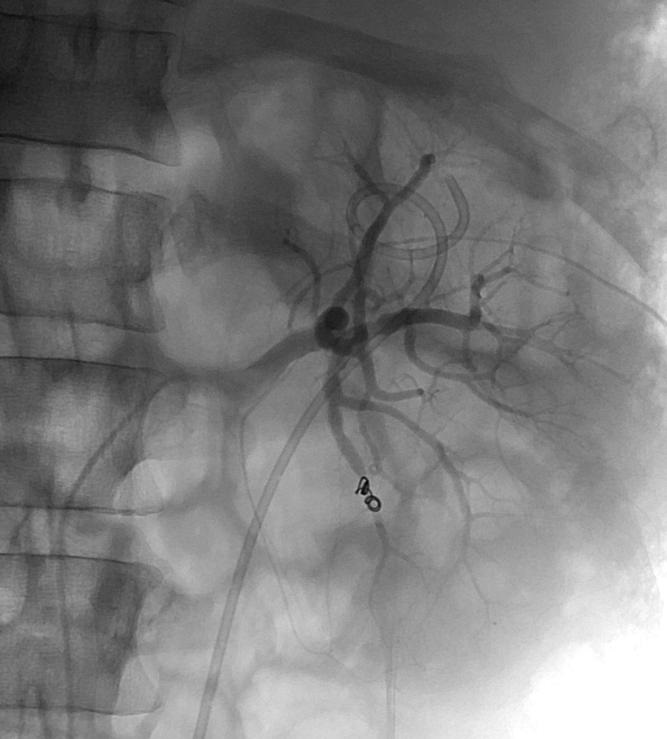

肾动脉损伤

AAST I & II 级损伤是低级别的损伤,III & IV 损伤(无血管损伤)为中等级别的损伤,而IV(有血管损伤)和 V级损伤是高级别的损伤【1】。

动脉栓塞在91%的病例,临床成功率为82%【2】。 肾损伤栓塞并发症<10%,包括感染、尿瘘和肾梗死【3】。 1. Incidence and management of penetrating renal trauma in patients with Multi organ Injury: Extended experience in an inner city trauma center. Journal of Urology Oct 2004;172:1355-1360 2. Cardiovasc Intervent Radiology 2005;28(1):38-47 3. Embolotherapy in renal trauma.Semin Intervent Radiology 1992;9:13-18 |